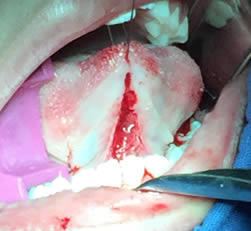

• Se realizó una incisión horizontal en la parte media del frenillo con hoja de bisturí No. 15 y mango No. 3, posteriormente se comenzó a cortar el frenillo de arriba abajo cuidando la anatomía de la región y la zona de las carúnculas sublinguales de los conductos de Wharton y Rivini. (Figuras 5 y 6).

Figuras 5 y 6. Incisión y corte del frenillo.